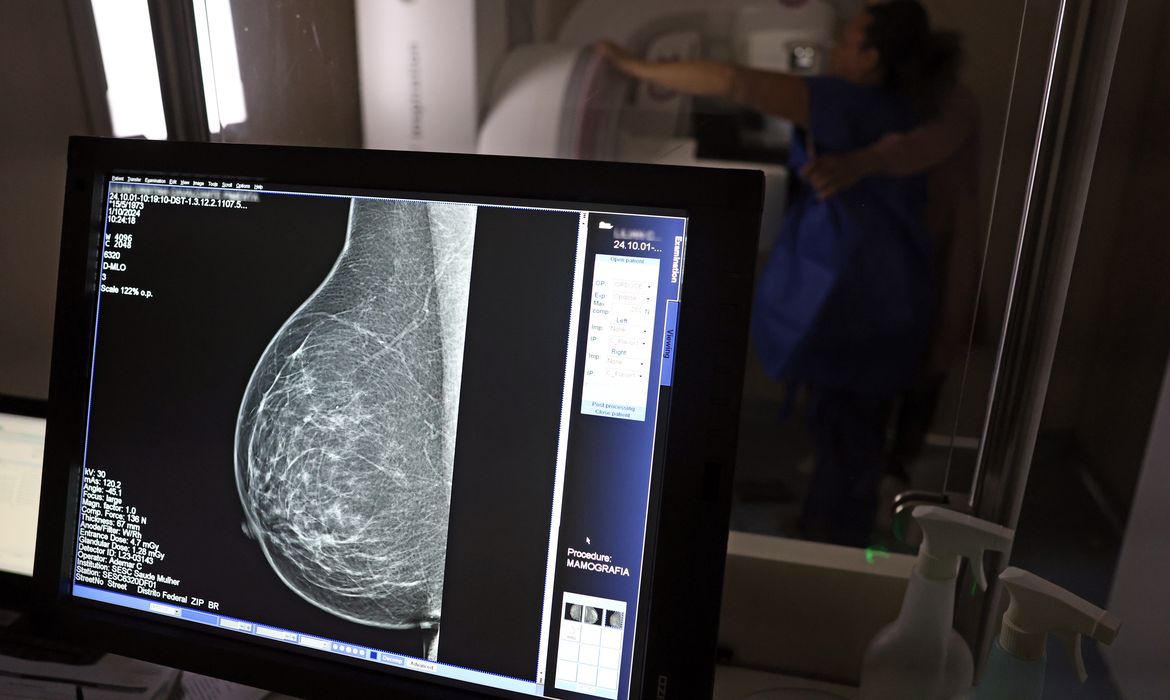

Ministério da Saúde passa a recomendar mamografia a partir dos 40 anos

O Ministério da Saúde passou a recomendar o acesso a mamografia, via Sistema Único de Saúde (SUS), para mulheres de 40 a 49 anos – mesmo que não haja sinais ou sintomas de câncer de mama. De acordo com a pasta, a faixa etária concentra 23% dos casos da doença, e a detecção precoce aumenta as chances de cura.

Até então, a orientação era que o exame fosse feito a partir dos 50 anos.

As mamografias via SUS em pacientes com menos de 50 anos, de acordo com a pasta, representam 30% do total, o equivalente a mais de 1 milhão apenas no ano de 2024.

Outra medida anunciada é a ampliação da faixa etária para o rastreamento ativo – quando a mamografia é solicitada de forma preventiva a cada dois anos. A idade limite, até então, era 69 anos. Agora, passa a ser 74 anos. Dados do ministério revelam que quase 60% dos casos de câncer de mama estão concentrados entre 50 e 74 anos.

Os números mostram que, em 2024, cerca de 4 milhões de mamografias para rastreamento e 376,7 mil exames diagnósticos foram realizados no SUS.